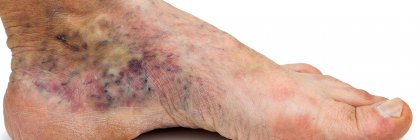

Nazwa zespołu objawów pochodzi od nadmiaru krwi żylnej, która zbiera się w poszerzonych splotach żylnych miednicy, w sąsiedztwie jajników, macicy, przymacicz i drogą zstępującą w obrębie ścian samej pochwy. Możliwe są różne rodzaje konfiguracji tego typu żylaków, z występowaniem nietypowo układających się żylaków na nogach włącznie. Żylaki na nogach będące pochodną niewydolności żylnej miednicy fachowo nazywane są żylakami atypowymi. Pojawiają się one zwykle po wewnętrznej i tylno-przyśrodkowej stronie uda, czasami wychodzą spod samych pośladków, bądź z okolicy sromu, zstępując ku dołowi.

Żylaki atypowe i pajączki widoczne na nogach, które powstają wskutek niewydolności żylnej miednicy, usuwane są zwykle w drugiej kolejności. W tym celu w Klinice Flebologii stosujemy najnowsze metody o znikomej inwazyjności dla Pacjenta (w znieczuleniu miejscowym, najczęściej bez cięć), takie jak: